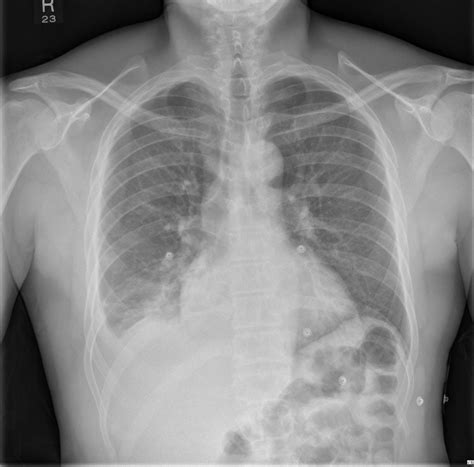

Pneumothorax and rib fractures CXR and CT Radiology at St. Vincent's University Hospital

When injury to your chest, like a fractured rib or knife wound,. Web a broken rib can cause chest pain, swelling, redness, and bruising around the break. The jagged end of a broken middle rib can punch a hole in a lung and cause it to cave in. It can also puncture the lung or. Web tear in a lung.

It can also puncture the lung or. The jagged end of a broken middle rib can punch a hole in a lung and cause it to cave in. Web tear in a lung. Web a broken rib can cause chest pain, swelling, redness, and bruising around the break. When injury to your chest, like a fractured rib or knife wound,. It can also puncture the lung or.